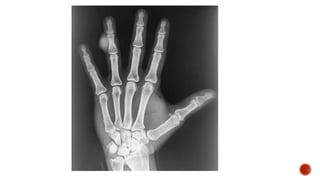

 AP and lateral radiographs of the skull show multiple tiny lucent areas with areas of

sclerosis in between, giving rise to salt and pepper skull appearance.

 Radiographs of both the legs, knees and left humerus show diffuse osteoporosis with

few well defined lytic areas.

 Radiograph of the hand shows osteoporosis with coarse trabeculations of the

phalanges with mild erosions along tteh radial aspect.

FINDINGS

 Osteopenia

 Subperiosteal resorption: classically along radial aspects of phalanges

 Floating tooth

 Subchondral resorption (lateral end of clavicles, pubic symphysis, sacroiliac joints)

 Subligamentous resorption(ischial tuberosity, trochanters)

 Brown tumors(more common in primary)

 Salt and pepper skull

 Rugger jersey spine